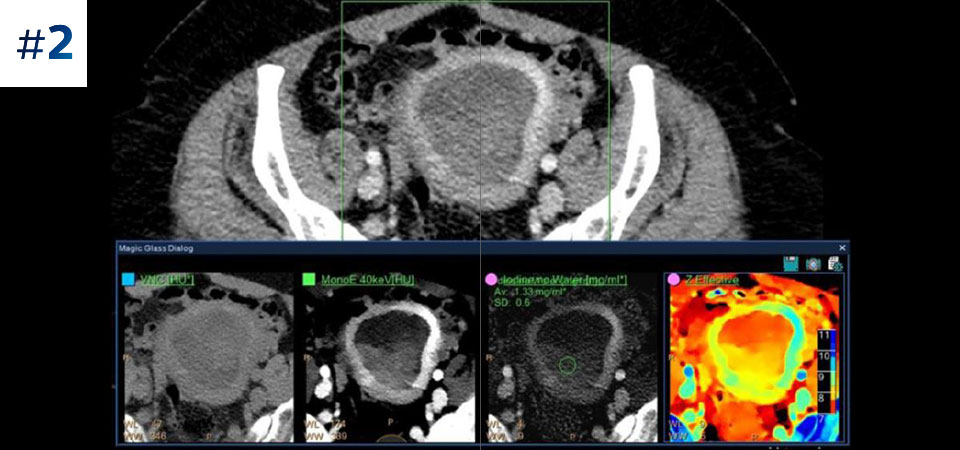

Reviewing spectral images

Go beyond conventional CT. See how layers of spectral-detector results can enhance your diagnostic confidence.

Abdomen pelvis